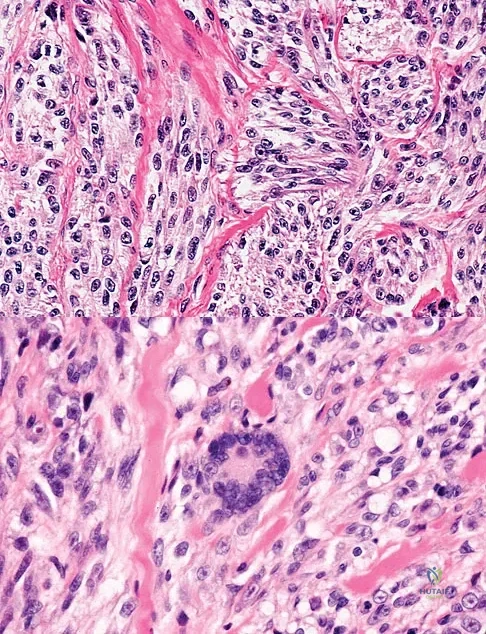

An 18-year-old boy reports increasing pain with weight bearing on his right leg and at night. Examination reveals swelling around the right midcalf. Radiographs and an MRI scan are shown in Figures 13a through 13c, and a biopsy specimen is shown in Figure 13d. What is the preferred treatment?